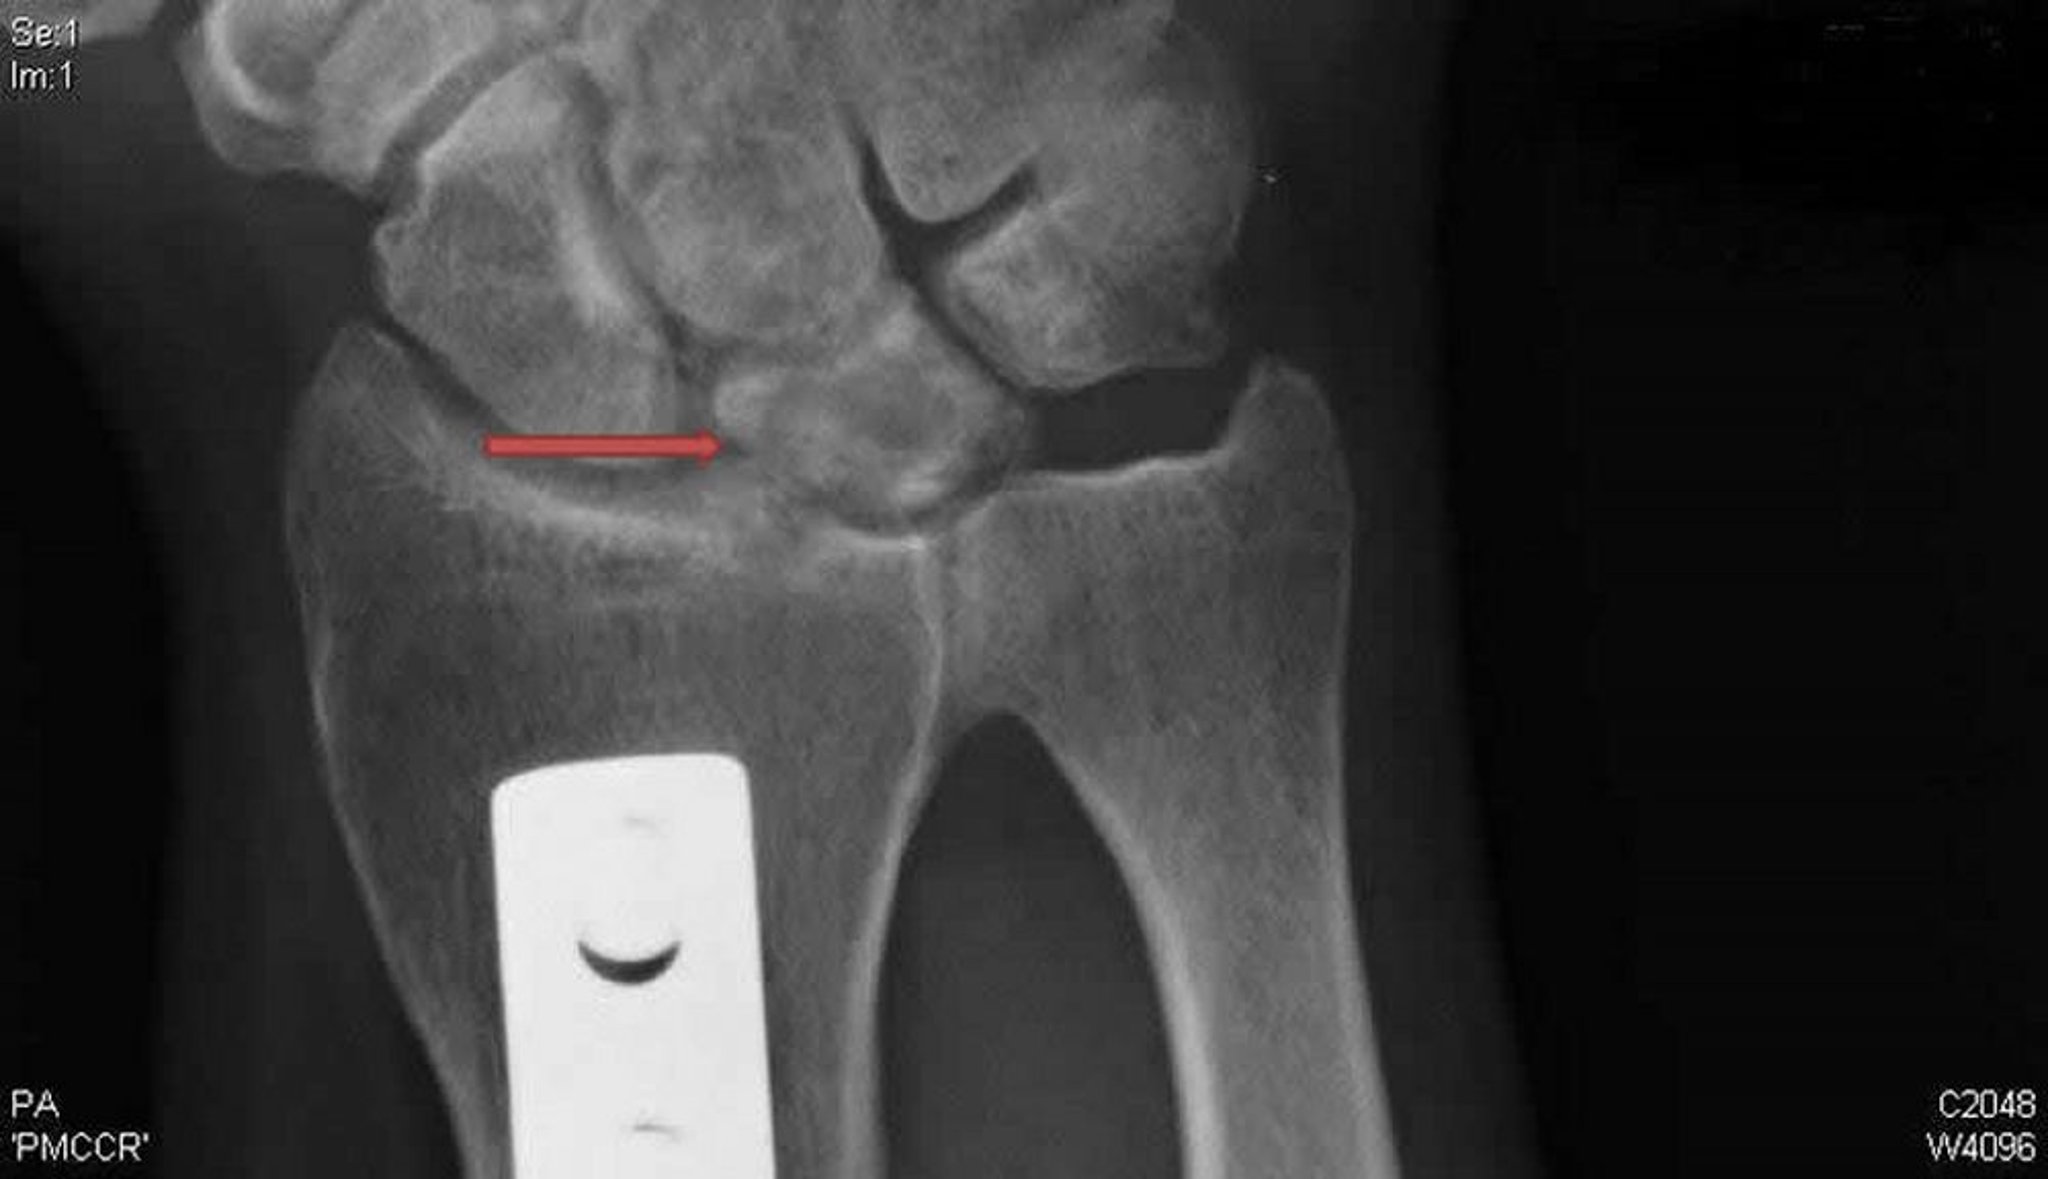

Enfermedad de Kienböck (radiografía posteroanterior)

Esta radiografía posteroanterior de la muñeca derecha muestra quistes y esclerosis del hueso semilunar (flecha) típicos de la enfermedad de Kienböck. La placa metálica evidencia una osteotomía de acortamiento radial que se realizó en un esfuerzo por descargar el peso sobre el semilunar y potencialmente tratar esta condición.

Radiografía cortesía de David R. Steinberg, MD.